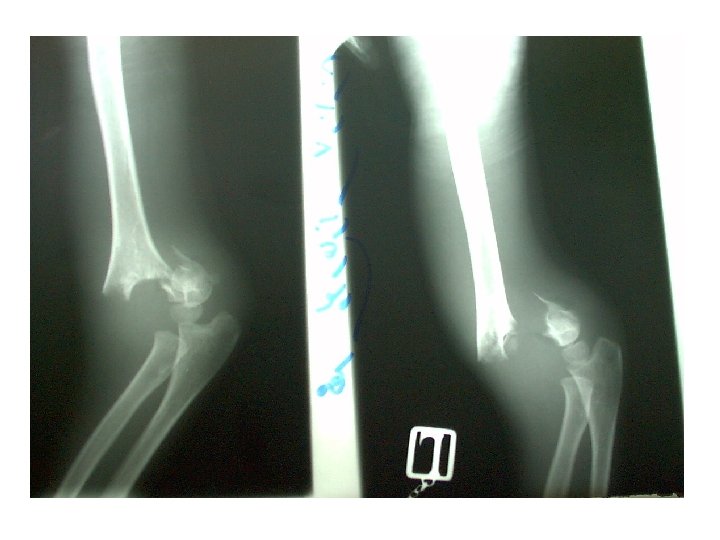

Open reduction 1 -displaced intra articular indications 2 -unstable Fr 3 -avulsion Fr 4

Open reduction 1 -displaced intra articular indications 2 -unstable Fr 3 -avulsion Fr 4 -Displaced pathologic Fr 5 - only operation indication 6 -Salter 3, 4 7 -compartment syn. 8 -NONUNION